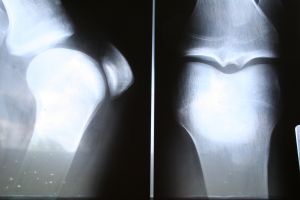

During the bone scan, your arm will be cleaned. A radioactive substance called a tracer will be injected into a vein in your arm and will travel through your bloodstream and into your bones. While the tracer is injected into your vein, the special camera will take pictures of the tracer within your bones. Areas that consume little or no amount of tracer appear as dark or “cold” spots. Cold spots could mean that there is a lack of blood supply to the bone or may also be an indication of various types of cancer. Areas of repair or fast bone growth consume more tracer and show up as bright or “hot” spots in the pictures. The hot spots may point out issues like arthritis, a fracture, an infection, or a tumor.